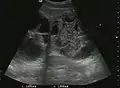

Liver abscess (2D and CEUS). 2D Examination reveals the fluid nature of the mass and imprecise delineation. CEUS examination shows congestion in the surrounding liver parenchyma and excludes a vascular tumor.

Liver abscess have heteromorphic ultrasound appearance, the most typical being that of a mass with irregular shapes, fringed, with fluid or semifluid content, with or without air inside. Doppler examination shows the lack of vessels within the lesion. CEUS exploration shows hyperenhancement during arterial phase close to the lesion, this being suggestive of a liver parenchymal hyperemia. During venous and sinusoidal phase the pattern is hypoechoic, and the central fluid is contrast enhanced. CEUS examination is useful because it confirms the clinical suspicion of abscess. In addition, it allows for an accurate measurement of the collection size and an indication regarding its topography inside the liver (lobe, segment).